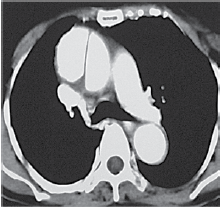

Homem de 37 anos é internado devido dor intensa em todo o braço esquerdo iniciada há 30 minutos. Encontra-se bastante ansioso e agitado pedindo ajuda. Pressão arterial (MSD): 230 x 170 mmHg. Uma tomografia com contraste foi realizada e ilustrada a seguir.

Em relação à dor no braço, é correto afirmar: